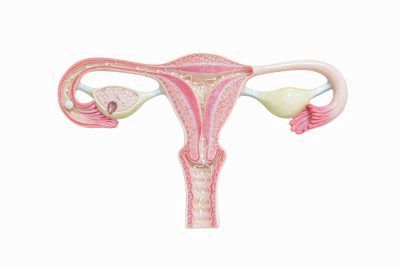

Місячні, менструація - це процес виділення отслоившегося зовнішнього шару матки (ендометрія) з кров'ю і лімфою через піхву.

Спочатку низький рівень естрогенів змушує гіпоталамус (частина мозку, що відповідає за ендокринну систему) виділяти рилізинг-гормони. Вони, в свою чергу, дають команду гіпофізу (ендокринній залозі біля основи мозку), і він виділяє безліч інших гормонів, які розносяться кровотоком по тілу. Коли вони потрапляють в яєчники (парні органи, сполучені з маткою), ті виділяють естрогени. Під впливом естрогенів починає зростати один з фолікулів, що містять яйцеклітини. Коли яйцеклітина готова, фолікул розкривається. Яйцеклітина виходить з нього (цей процес називається овуляцією) і подорожує по фаллопієвій трубі до матки.

Саме в цей час найбільш ймовірно зачаття, якщо всередині маткової труби яйцеклітина зливається зі сперматозоїдом, що піднялися з піхви на матці в цей канал. На місці фолікула, що лопнув залишається жовте тіло, що виділяє гормон прогестерон. Під впливом естрогенів і прогестерону слизова матки ущільнюється з 1 до 10 мм, робиться більш пухкої, набухає, наповнюється кров'ю і лімфою. Якщо зачаття відбувається, то вже запліднена яйцеклітина спускається з фаллопієвої труби по стінці матки і закріплюється на ній. Якщо зачаття не відбувається, то після декількох днів частина зовнішнього шару слизової матки (ендометрій) починає відшаровуватися невеликими шматочками. Слиз і кров з дрібних сосудиков змивають ендометрій через трохи розкрилася шийку матки в піхву, з якого рідина витікає назовні. Ці виділення і називають місячними.